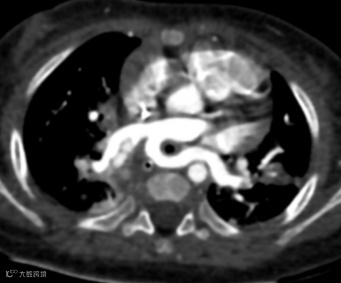

患儿,女,5月龄,喘鸣和反复胸部感染。

胸部CT增强图像如下:

左肺动脉起源异常,由右肺动脉发出,在气管隆突上方与食管之间形成不完整的环状结构。双肺散在分布多发实变影。

左肺动脉吊带,伴双肺感染